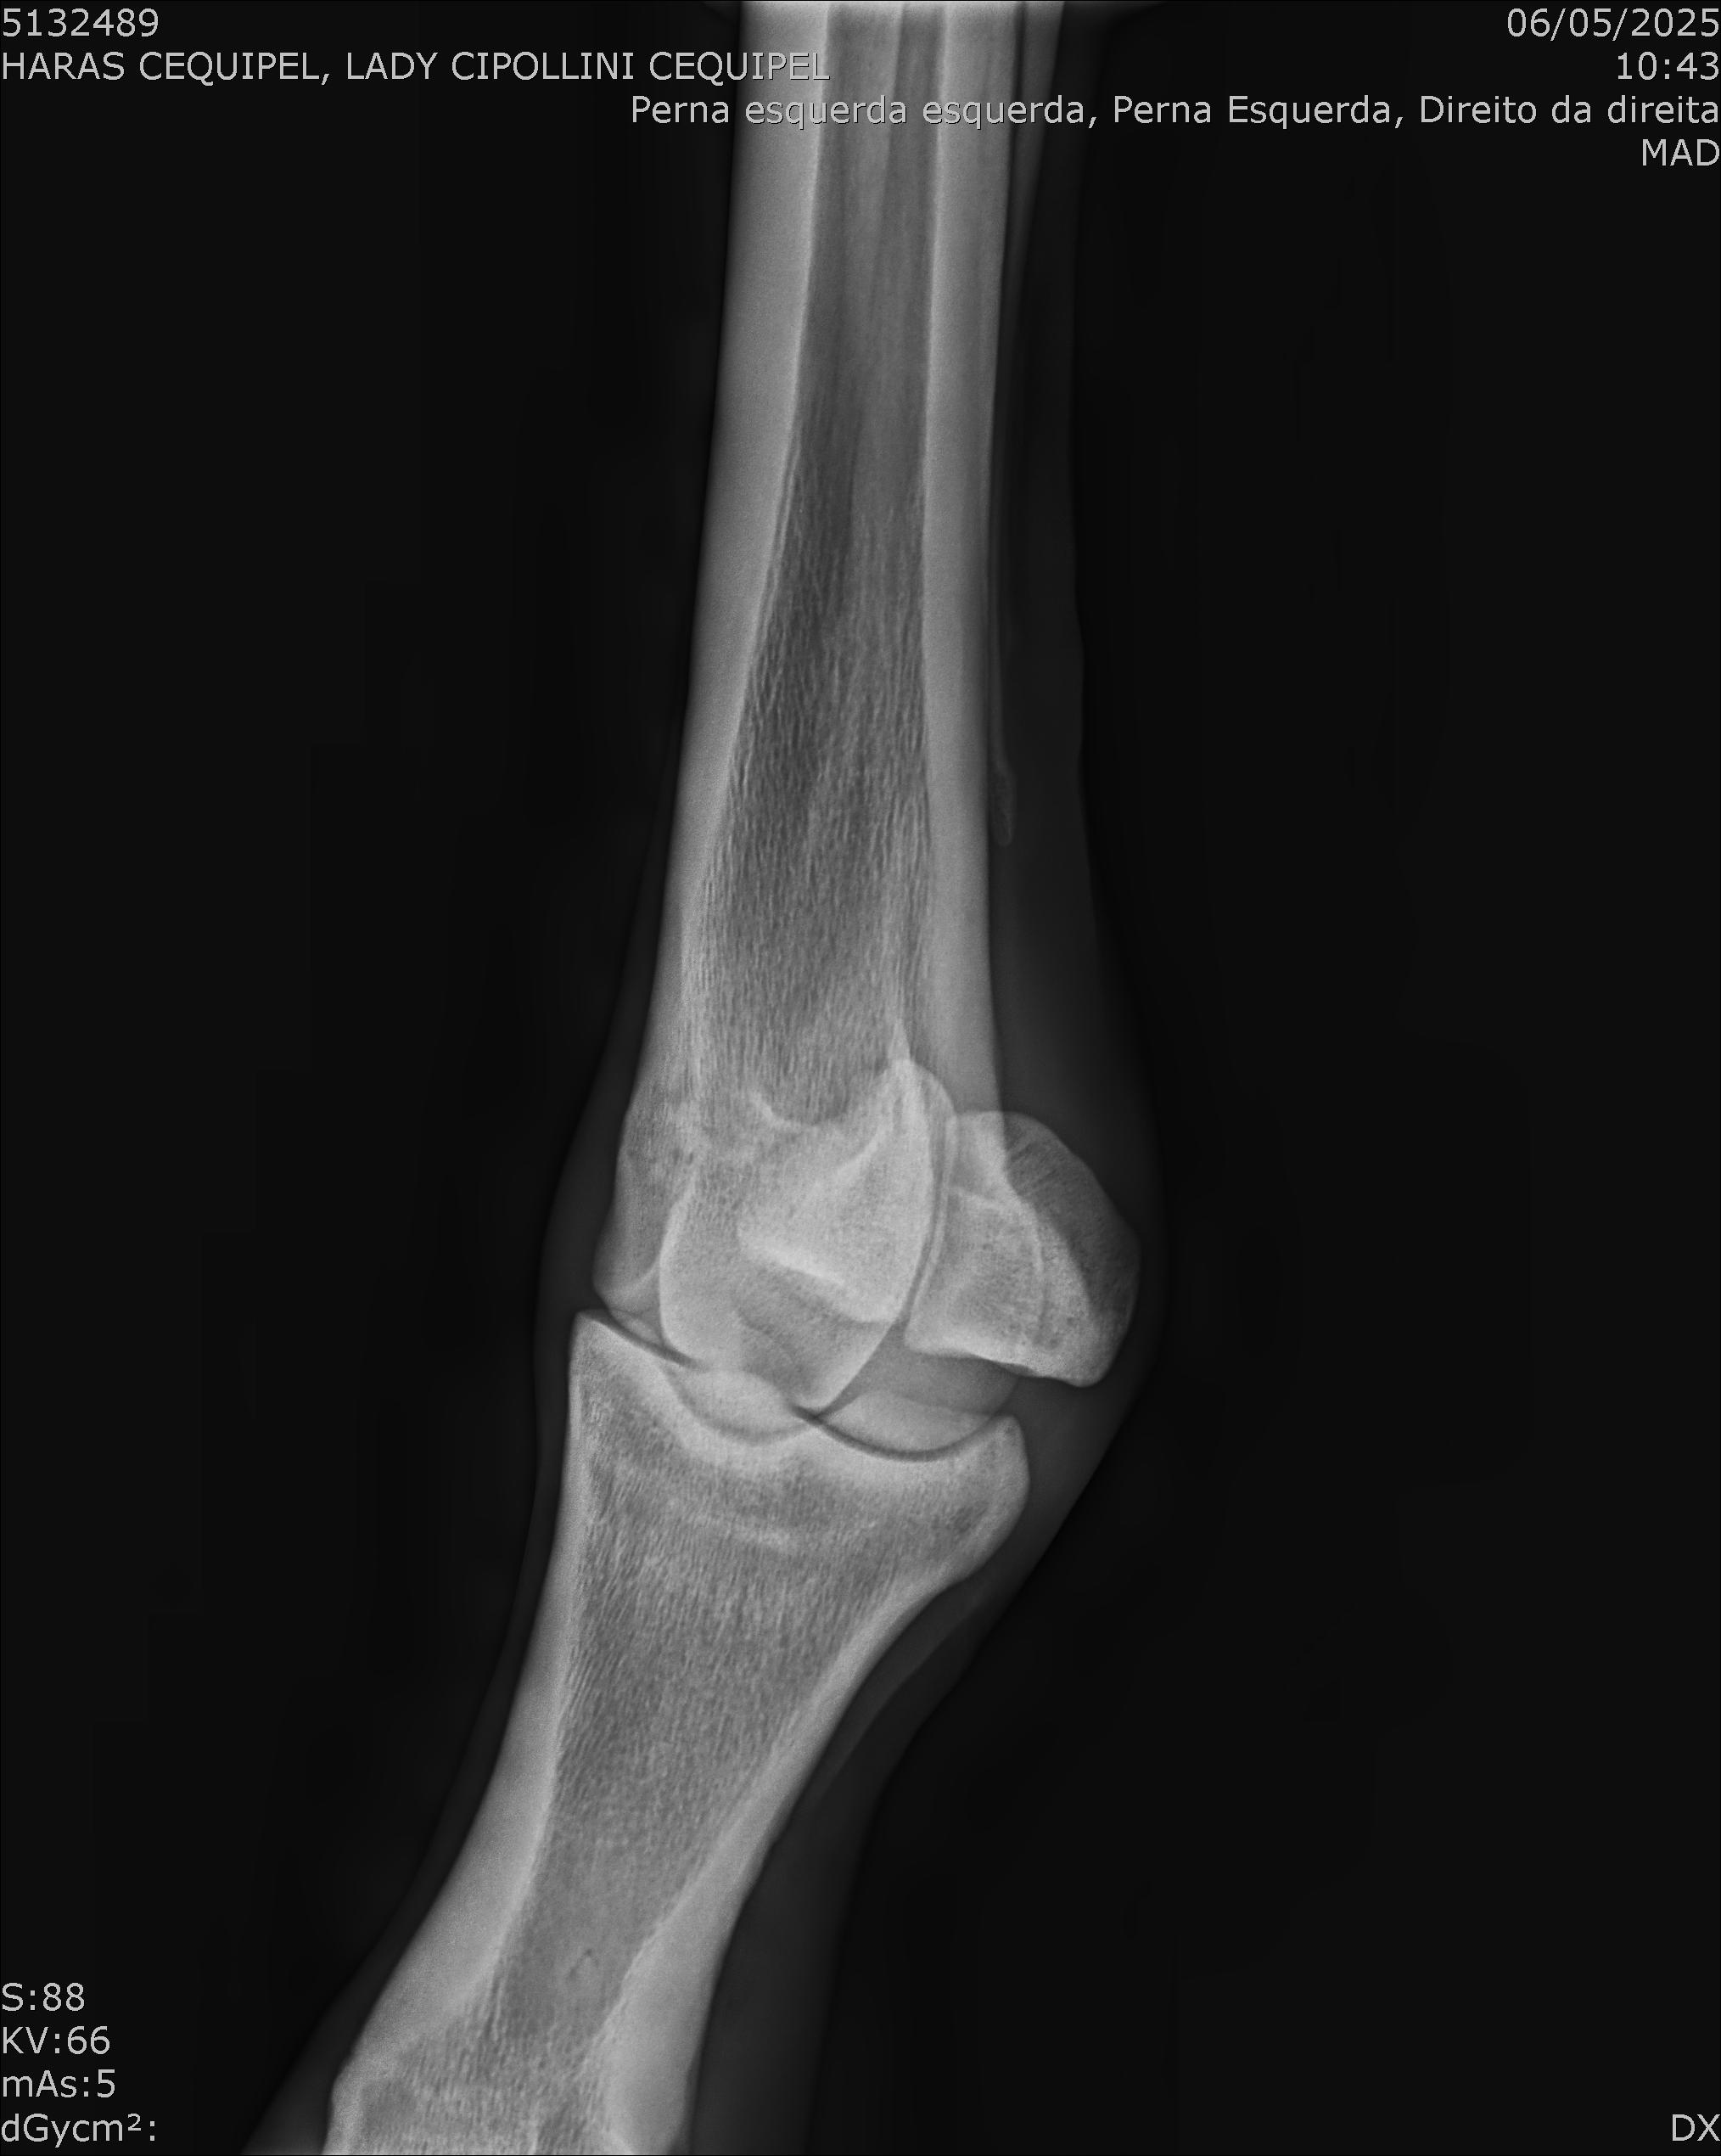

:: RAIOS-X DO LOTE